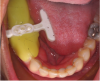

Fig. 16 through Fig. 18 The CEREC Guide was made in the office from a thermoplastic material (yellow). Initially, a radiographic insert (white) was embedded and placed in the mouth during the CBCT scan. After the implant was planned, a drill guide (clear) was milled and inserted into thermoplastic housing. The guide was ready for surgery.

Figure 16

Figure 17

Figure 18